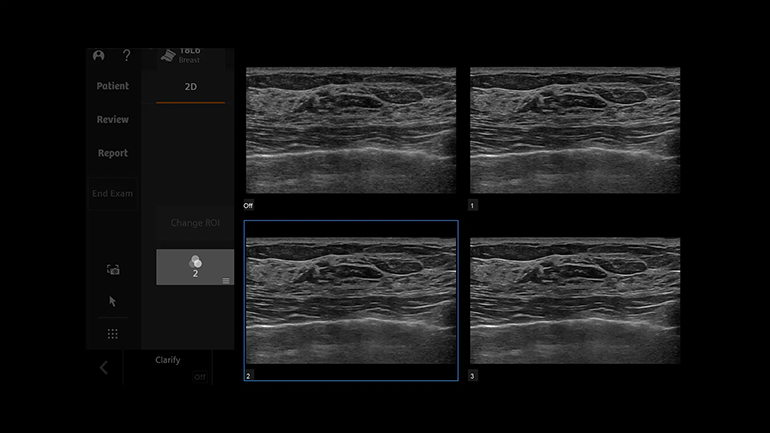

Высокая разрешающая способность благодаря матричному монокристальному датчику с фазированной решеткой. Основой любого датчика является пьезоэлектрический преобразователь. Монокристальная матричная конструкция датчиков обеспечивает высокую чувствительность получаемого изображения и широкую полосу пропускания при проведении наиболее важных исследований с помощью абдоминальных и кардиологических датчиков. Более широкая полоса пропускания эхо-сигнала улучшает визуализацию на глубине, разрешение по вертикальной оси и чувствительность, обеспечивая таким образом большую глубину проникновения и четкость получаемых изображений. Технология UltraArt — одновременный вывод четырех изображений в режиме реального времени на сенсорный экран с предустановленными различными настойками визуализации. Инновационная технология обработки эхо-сигнала UltraArt Universal Image Processing компании Siemens Healthineers позволяет выводить изображения на экран с предустановленными программными настойками. Выбор параметров визуализации можно определить одним нажатием кнопки на четырехкадровом дисплее в режиме реального времени. Эта технология позволяет улучшить контрастное разрешение различных анатомических структур, повысить качество и уровень согласованности исследований среди разных пользователей благодаря исключению возможности выбора неправильных сочетаний отдельных параметров сканирования.

Технология UltraArt — одновременный вывод четырех изображений в режиме реального времени на сенсорный экран с предустановленными различными настойками визуализации. Инновационная технология обработки эхо-сигнала UltraArt Universal Image Processing компании Siemens Healthineers позволяет выводить изображения на экран с предустановленными программными настойками. Выбор параметров визуализации можно определить одним нажатием кнопки на четырехкадровом дисплее в режиме реального времени. Эта технология позволяет улучшить контрастное разрешение различных анатомических структур, повысить качество и уровень согласованности исследований среди разных пользователей благодаря исключению возможности выбора неправильных сочетаний отдельных параметров сканирования. Оптимизация ультразвукового исследования с помощью технологии Auto TEQ. Технология автоматической оптимизации AutoTEQ подстраивает соответствующие параметры визуализации, позволяя свести к минимуму действия врача-диагноста по настройке сканера. В B-режиме и в импульсном допплеровском режиме можно настроить одновременно несколько параметров сканирования — например, общее усиление сигнала, шкалу скорости и фильтр помех от движения стенок сосудов при пульсовой волне.